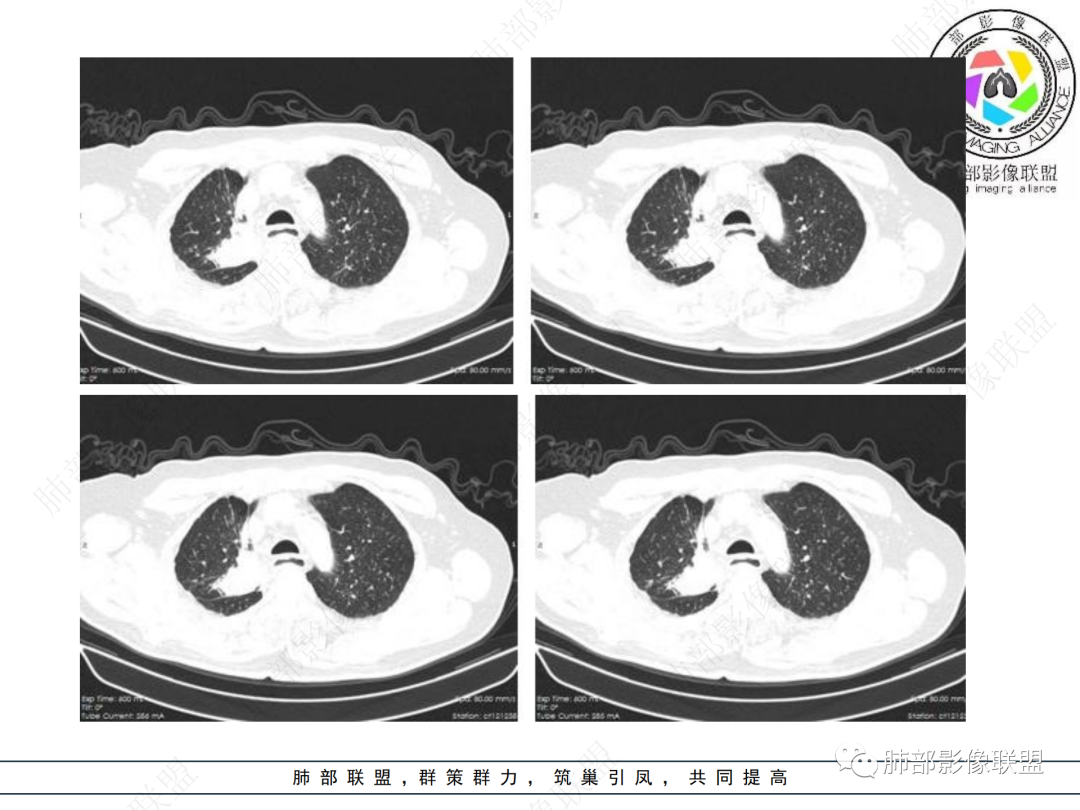

男性,69岁 反复咳嗽2年余,加重3天入院。CT示右肺上叶尖段不规则实变影,周边伴条索影,支气管未见明显堵塞,增强不均匀强化,考虑为恶性,腺癌可能

男,69,反复咳嗽2年,加重3天入院,右肺上叶软组织密度肿块影,边界尚清晰,边缘见毛刺及胸膜牵拉,右肺上叶支气管壁增厚,增强扫描不均匀性强化,考虑腺癌可能,鉴别炎性病变。

老年男性,病史2年,加重3天

提示慢性病史

加重3天——提示有急性病变,或原病变突然加重

右上胸廓较对侧慢性缩小

右上叶体积缩小

慢性病变有

内部支气管近端狭窄,远端粘液栓

结核要考虑下

内部血管也通畅

边缘也算平直

不踏实的是这里稍膨隆

恶性待排吧